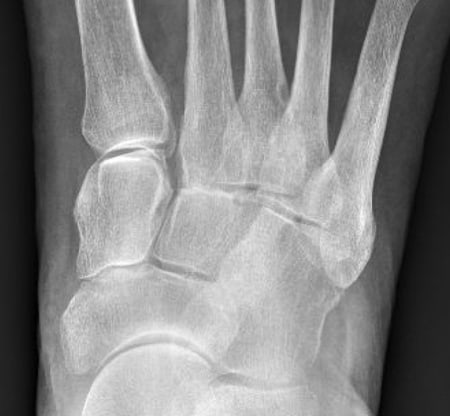

CT präoperativ

Zeigt deutliche Arthrose im TMT Gelenk.